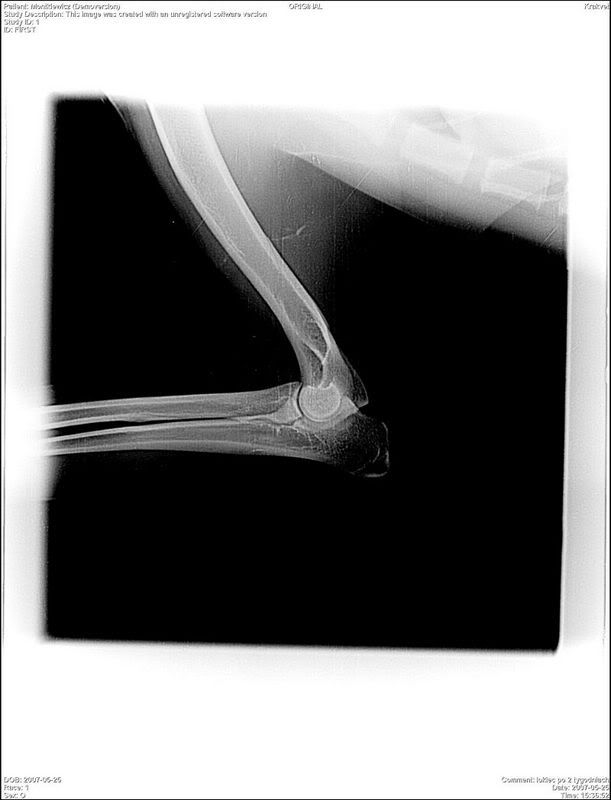

Nugatowa Posted May 26, 2007 Author Posted May 26, 2007 Cóz to za konina zagościła w naszej galerii :mad: :mad: :evil_lol: A my wczoraj ściągneliśmy gipsik :multi: :multi: Doktor mówi, że kość się idealnie zlała :multi: :multi: :multi: za 2 tyg do kontroli i do tego czasu tylko na smyczy :-( :-( ale jak przeszlismy gips to i przejdziemy to Aha Nugx miał komputerowe RTG jako pierwszypies w klinice japonskim sprzętem na licencji o to one. http://i50.photobucket.com/albums/f309/Nugatowa/rentgendobry.jpg Wczoraj zaliczył pierwsza kąpiel rehabilitacyjną w szarym mydle :diabloti: Potem była wielka obraza majestatu A potem juz żwyioł na dywanie A tutaj mina przy której zawsze wymiękam I po wysuszeniu Quote